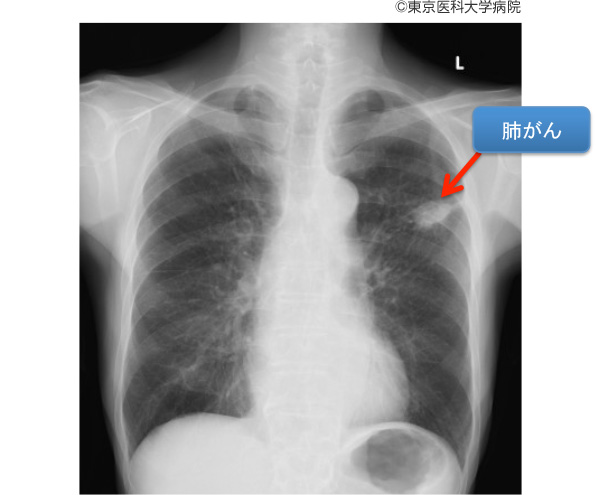

肺がんは、初期段階で診断することが難しい重篤な疾患です。しかし、研究者たちは肺がんの早期発見に役立つ、より効果的な診断ツールの開発に取り組んでいます。早期発見は治療をより効果的にするのに役立ちます。

低線量 CT スキャンでは、従来の CT スキャンよりも被曝する放射線量が少なくなります。また、以前は肺がんのスクリーニングに使用されていた胸部 X 線検査よりも正確です。肺がん検診について詳しくはこちらをご覧ください。